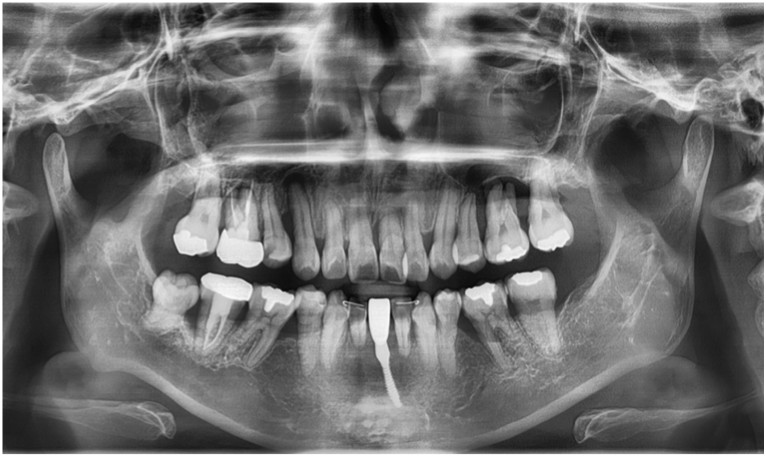

먼저 구강 내를

확인해 보았더니

다수 치아의 상실로 인해

치아의 배열이 흐트러져 있고,

잔존 치아들도

동요도가 심한 상태였는데요.

정밀한 검사를 위해

파노라마 사진을

촬영해 보았더니

만성 치주염으로 인해

다수 치아 상실과

심각한 골소실이 보였으며

이로 인해 양측 어금니 부위의

교합 및 수직 고경이 소실된 상태였습니다.